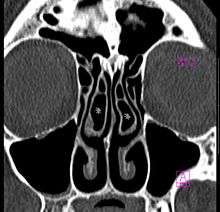

Concha bullosa

A concha bullosa is a pneumatized (air-filled) cavity within a turbinate in the nose.[1] (Concha is another term for turbinate.) Bullosa refers to the air-filled cavity within the turbinate.[1] It is a normal anatomic variant seen in up to half the population. Occasionally, a large concha bullosa within a turbinate may cause it to bulge sufficiently to obstruct the opening of an adjacent sinus, possibly leading to recurrent sinusitis.[1] In such a case the turbinate can be reduced in size by endoscopic nasal surgery (turbinectomy). The presence of a concha bullosa is often associated with deviation of the nasal septum toward the opposite side of the nasal cavity.[2] Although it is thought that sinusitis or sinus pathology has relation to concha bullosa, no strong statistical correlation has been demonstrated.[1]